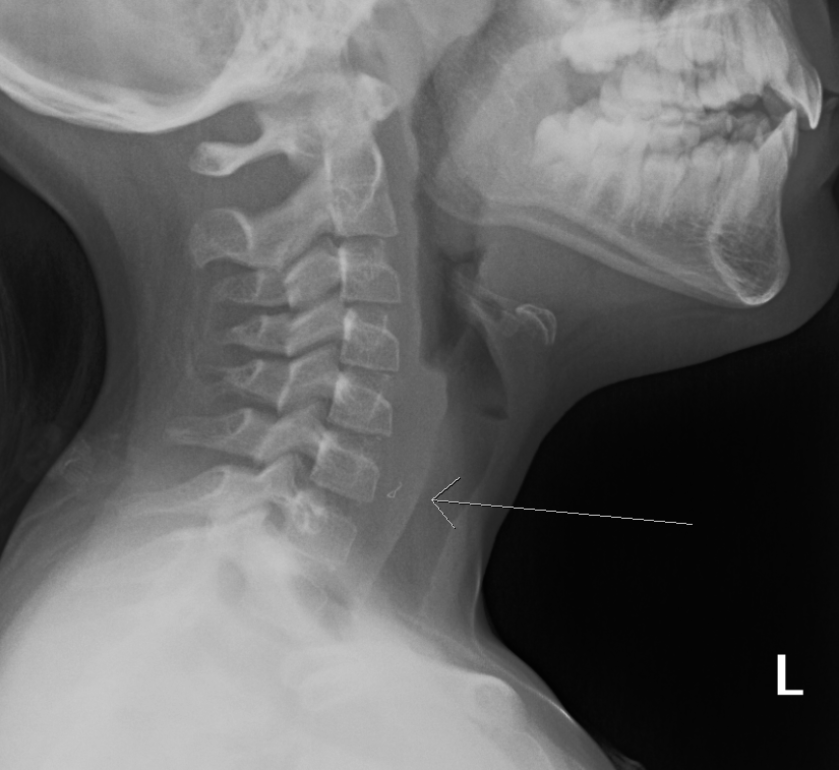

“Most of the time,” I tell her mother, “when people feel something in their throat, or their esophagus, it’s just that something left a scratch, and it’s gone. I write an order on the chart – soft tissue neck – and I point them toward x-ray. “It is possible, though, that there’s a wire stuck there. And if there is, it should show up on the x-ray.”

Ten minutes later, they’re in a different room. I see them in there – before I have a chance to look at the x-ray. I ask my assistant to pull it up on the screen behind me. I turn around and study it.

I turn to her mom. “It’s there,” I say. “Clear as day. Stuck at the top of her esophagus.”

I show them the X-ray. I tell her that our gastroenterologist isn’t comfortable with 8 year old passages, and that I’ll have to make a call to the pediatric hospital and have her transferred there. “I just hope that it isn’t embedded too far into the tissues of the esophagus,” I tell her mother quietly. “There are times when they can’t get these wires out.”